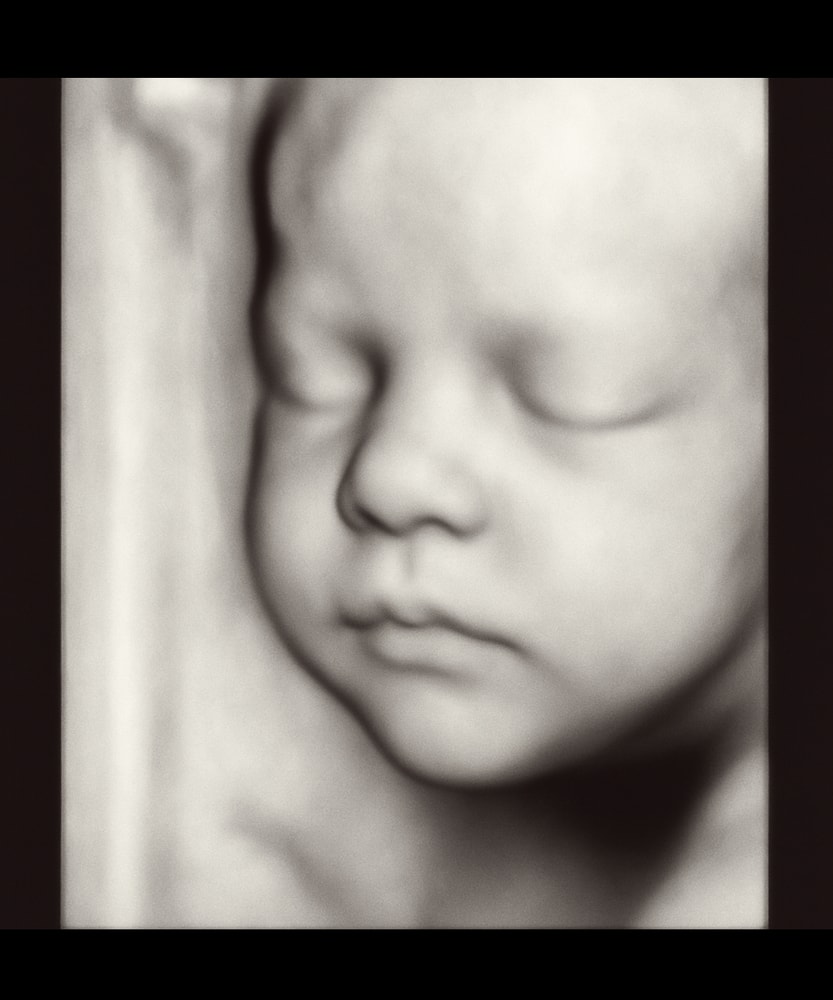

Вот наша малышка! Сейчас 29 недель

Девочки, привет! Сходила на узи 4D. Четкость конечно не очень… постоянно закрывала лицо ручками. Но самое главное - у ребенка все хорошо! Весим уже 1100 гр. Обязательно еще схожу!